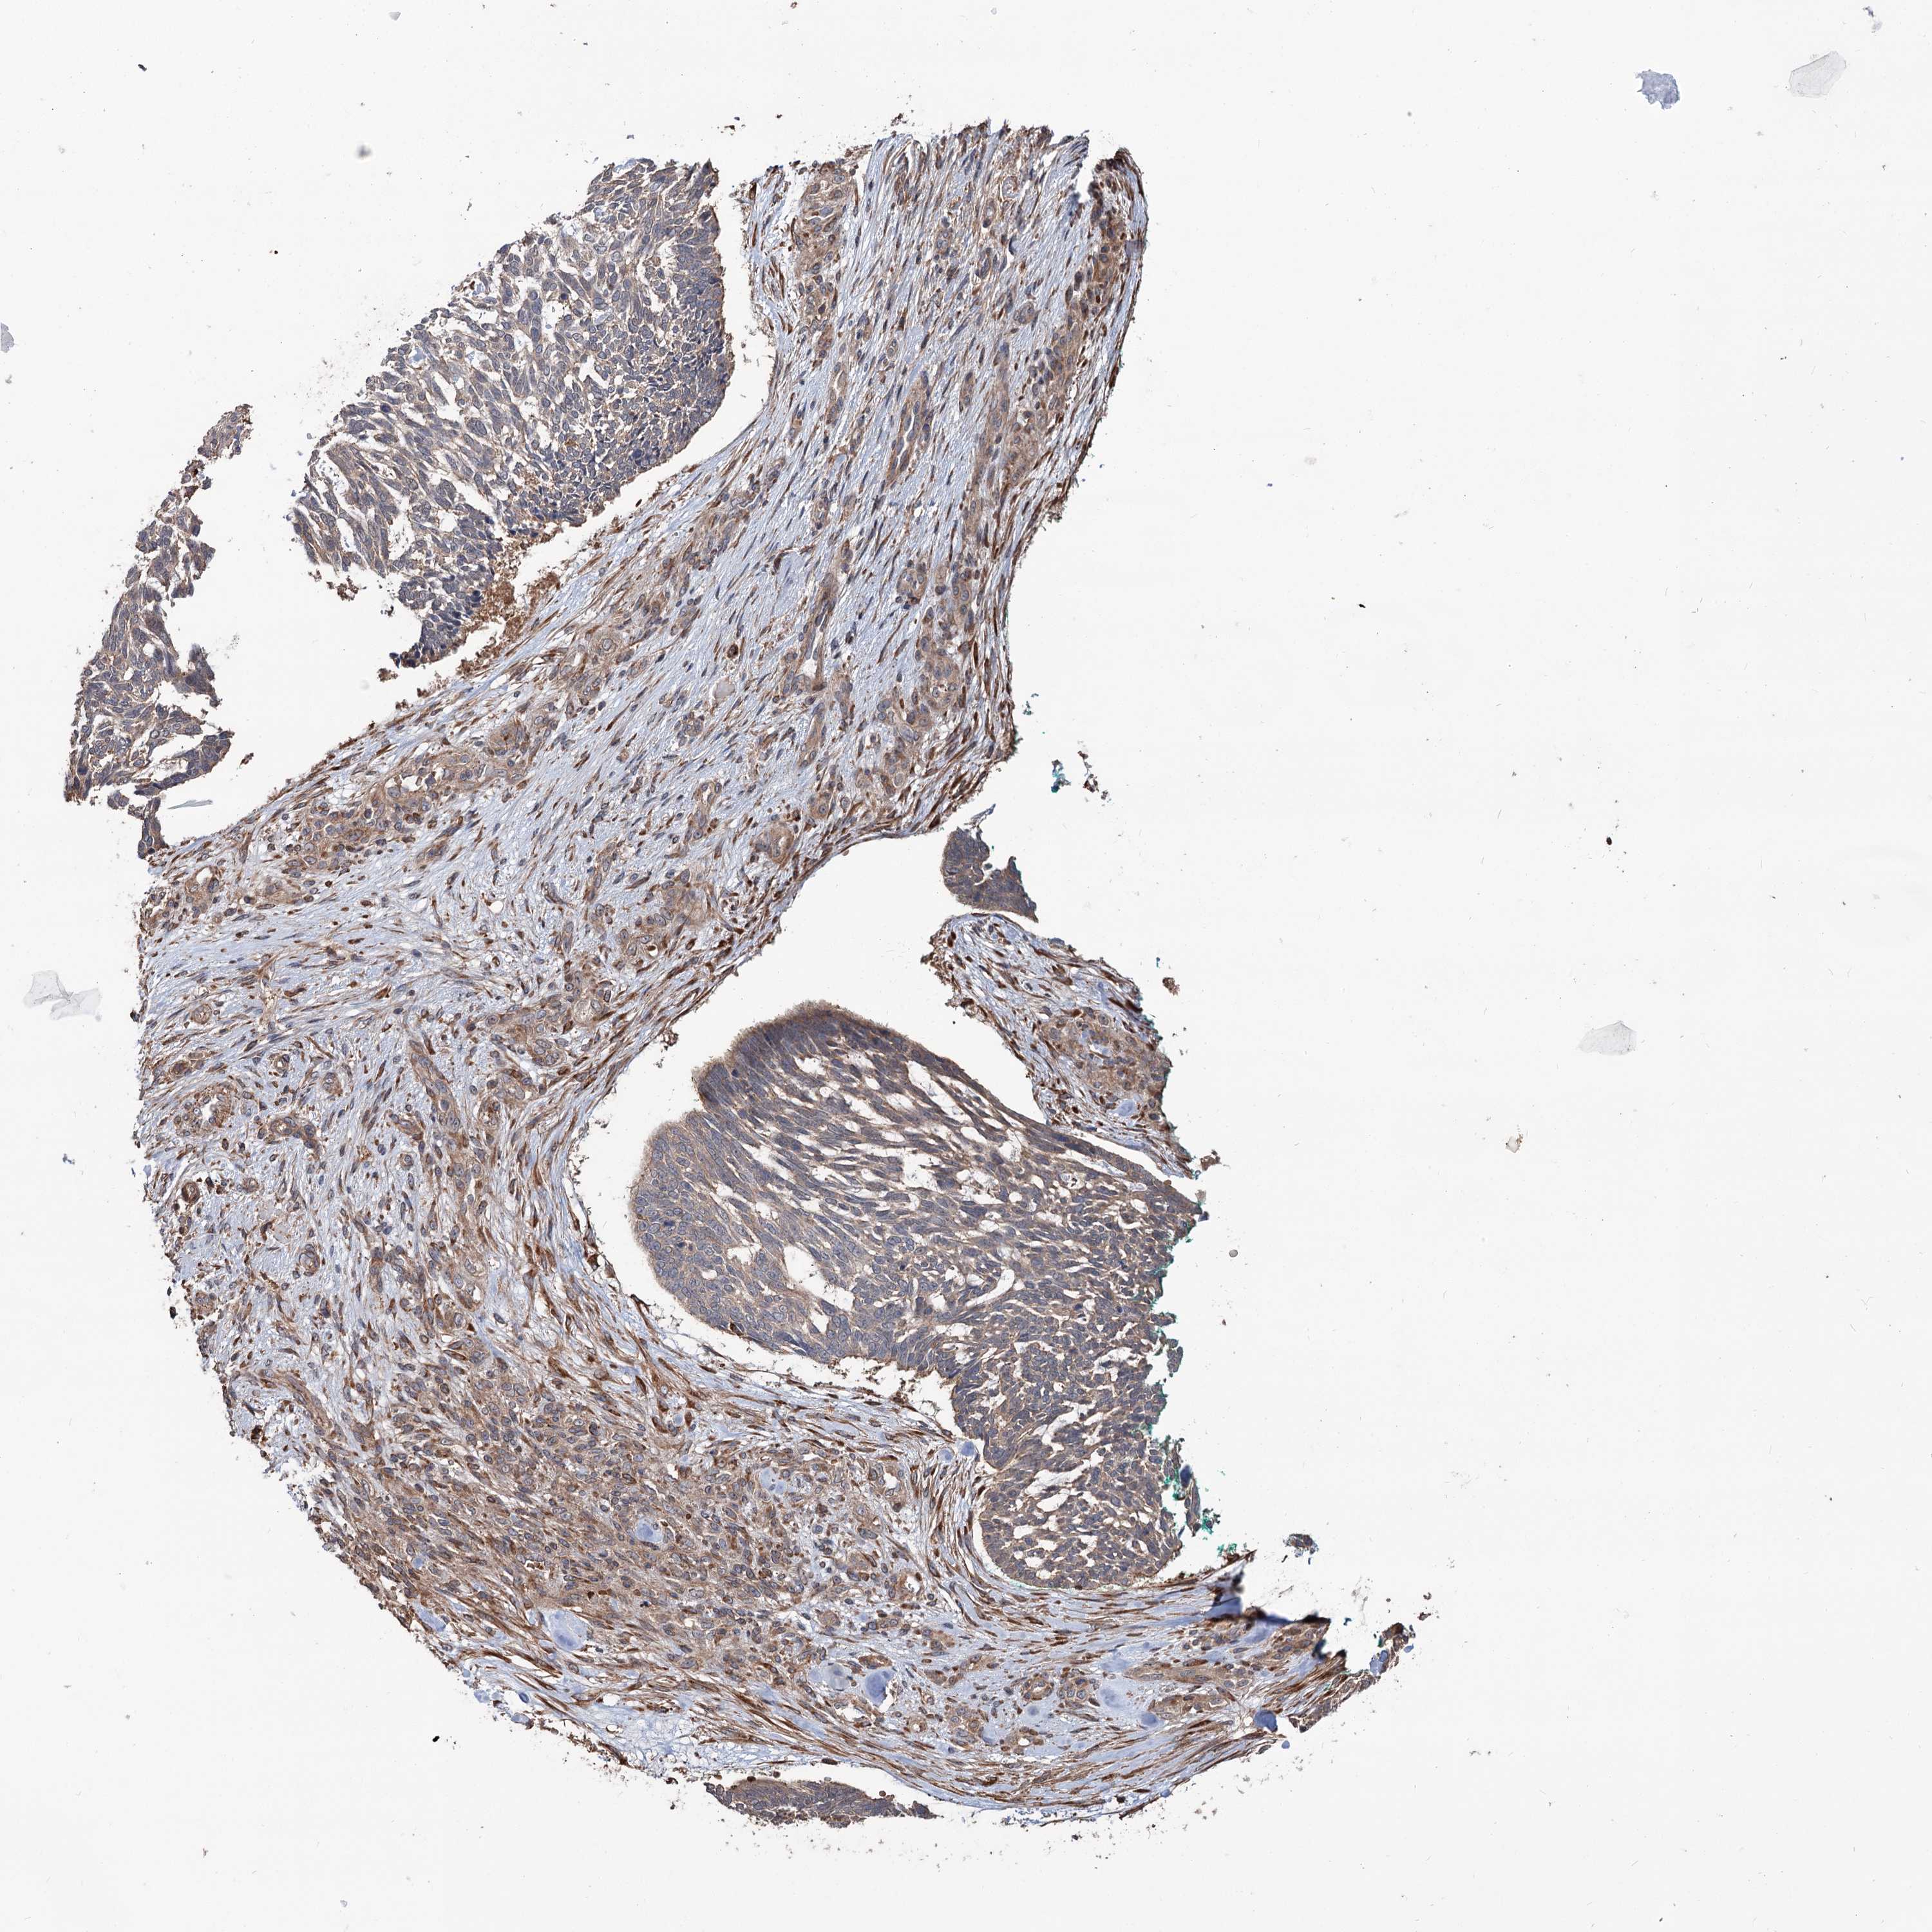

SKIN CANCER - Protein expressioni

A mouse-over function shows sample information and annotation data. Click on an image to view it in a full screen mode. Samples can be filtered based on level of antibody staining by selecting one or several of the following categories: high, medium, low and not detected. The assay and annotation is described here.

Each image is clickable and will lead to virtual microscopy that enables deeper exploration of all samples and also displays staining intensity scores, fraction scores and subcellular localization as well as patient and tissue information for each sample.

Antibody HPA038856

Staining

High

Intensity

Strong

Quantity

>75%

Location

Nuclear

Squamous cell carcinoma, NOS